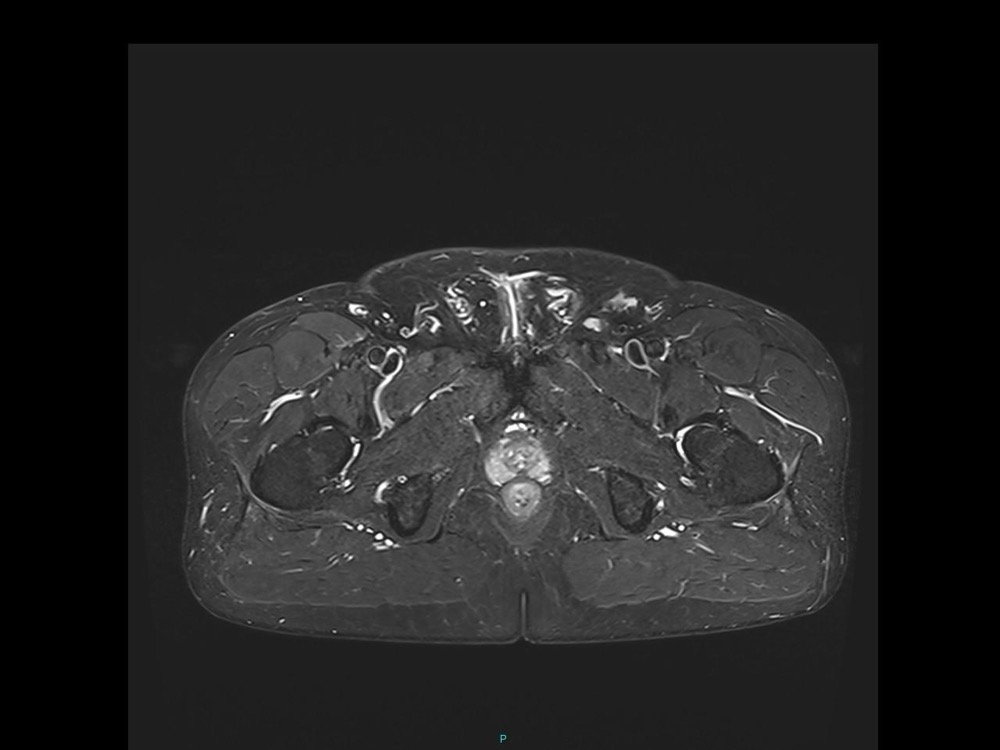

Bone Club

Olivia Fortucci 11/01/2023